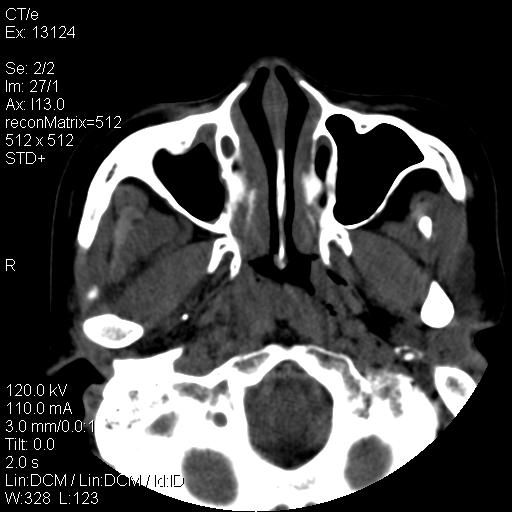

标题: CT18257:女,29岁,右下磨牙痛 [打印本页]

标题: CT18257:女,29岁,右下磨牙痛

女,29岁,右下磨牙痛,因产后2月,故未治疗。现右颌肿痛伴张口困难。请大家看看右侧鼻咽部、口咽部是否

2.右侧上颌窦炎症、两侧下鼻甲肿大

1)考虑右侧下颌区软组织脓肿(牙源性)。2)鼻咽部炎性改变;建议追踪复查。3)右侧上颌窦炎。4)双侧下鼻甲黏膜肥厚。

1)考虑右侧下颌区牙源性软组织脓肿。2)右侧上颌窦炎。3)双侧下鼻甲黏膜肥厚。4)鼻咽部炎性改变;建议追踪复查。